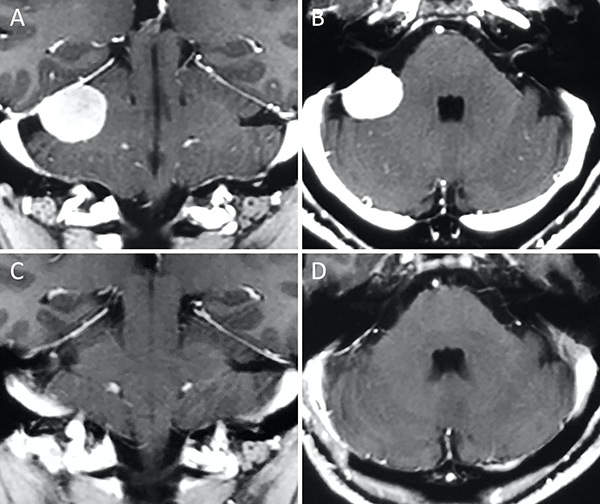

Figura 3. Meningioma clival. A-B: RM preoperatoria; C-D: RM postoperatoria.